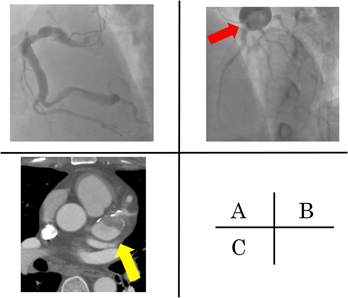

Fig. 1 The coronary images before operation at previous hospital

(A) (B) The coronary angiography images. The right coronary artery was dilated on the whole and a giant aneurysm can be observed in the left main trunk (red arrow). No stenoses were seen. (C) The cardiac CT image. A thrombus can be observed in the left main trunk, as well as coronary calcifications (yellow arrow). The automatically-calculated Agatston score, which is the sum of maximal CT value for the area of each coronary arterial calcification using axial plane images, is 1622.5 (left main trunk, 1579.4; left circumflex coronary artery, 0; left anterior descending artery, 0; right coronary artery, 43.1).

A 38-year-old man, diagnosed with KD at age 7, was admitted to our hospital with a giant coronary aneurysm. Medical data on the initial KD diagnosis were not available. However, the coronary angiography at 2 years old showed that coronary aneurysms were observed at segment 1, 2 and 5. He was treated at our hospital until the age of 13, but there were no hospital visits since then. At his current admission, he was transported to previous hospital because of sudden chest pain. The blood test showed that creatine phosphokinase was 638 IU/L and an asynergy at inferior wall was observed with echocardiography while the cardiac function was normal. T-wave abnormality or the other specific findings of acute coronary syndrome were not seen with electrocardiogram. He was suspected with myocardial infarction. With the coronary angiography, the right coronary artery was dilated on the whole and a giant coronary aneurysm was observed at the left coronary artery while there were no stenoses (Fig. 1A, B). His condition improved with heparin and nicorandil and he was discharged under the treatment with oral clopidigrel and warfarin. Two weeks later, he complained of chest pain again, and was transported to the hospital. The blood test showed not elevated creatine phosphokinase but slightly elevated troponin T. The cardiac CT had located a giant coronary aneurysm, three calcified lesions, and the obstruction of a coronary artery by a thrombus. His Agatston score, which assesses the severity of CAC using the cardiac CT calculated with the CT levels more than 130 HU and their areas, and which is strongly associated with the cardiovascular event onset, was 1622.5 (left main trunk, 1579.4; left circumflex coronary artery, 0; left anterior descending artery, 0; right coronary artery, 43.1) (Fig. 1C).4, 5) He was diagnosed with myocardial infarction again. After his symptom rapidly improved with heparin and nicorandil, he was transferred to our institution for the operation. At the time of admission, his body weight was 113 kg, with a body mass index of 36.9 kg/m2. His morbid obesity was complicated with hypertension (systolic/diastolic blood pressure, 146/45 mmHg at admission), which we treated with 20 mg/day of azilsartan medoxomil; and hyperlipidemia (total serum cholesterol, 155 mg/dL; total serum triglycerides, 349 mg/dL) which we treated with 5 mg/day of rosuvastatin. The patient underwent a thrombectomy and coronary artery bypass grafting (left internal thoracic artery to obtuse marginal coronary artery and right internal thoracic artery to left anterior descending artery, segment 8) (Fig. 2). The giant aneurysm was removed because it triggered blood clots and they flowed into the periphery of the coronary artery, which caused myocardial infarction during surgery. Pathological examination revealed atherosclerosis-like lesions, including the accumulation of foam cells, hyalinization, cholesterol clefts, and granular calcification (Fig. 3). After surgery, carotid ultrasonography and pulse wave velocity results were normal, which indicated that the patient did not have atherosclerotic lesions or calcifications in the other arteries. Composition analysis with infrared absorption spectrometry revealed that the CAC was composed of >98% calcium phosphate with carbonate, similar to carbonate apatite (Fig. 4). The dual-energy CT showed that the median EANs of the calcifications was 13.41 (11.14–16.38), which resembled the EAN of CAC caused by atherosclerosis, 13.8 (Fig. 5).6) These results indicated that the composition of KD-induced CAC was similar to that of atherosclerosis. The patient has not exhibited any complications after the surgery, as confirmed by a post-operative follow-up of 6 months.